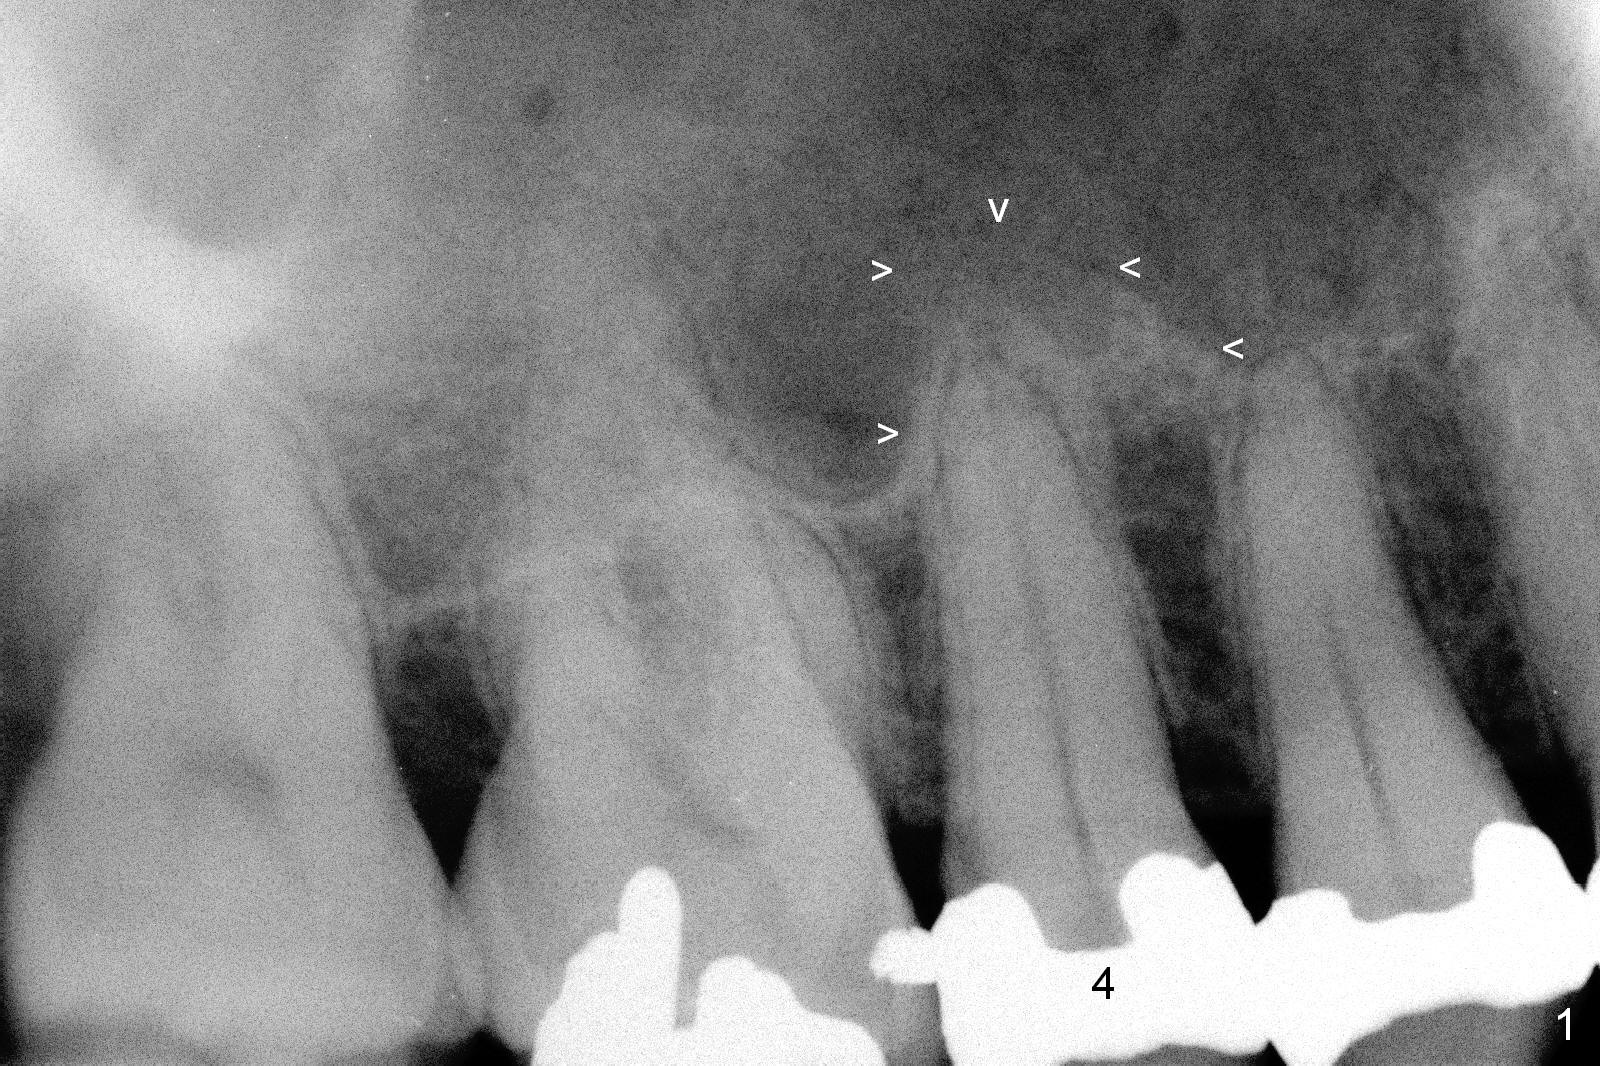

A 55-year-old man had 2nd caries with pulpitis at the tooth #4 a year ago (Fig.1), requiring RCT (Fig.2). The tooth fractured biting on a piece of nut shell inside a moon cake recently (Fig.3 *, 5, 6). There is a sinus septum apical to the apex of the affected tooth (Fig.1-3 arrowheads). After extraction and Metronidazole socket treatment, an immediate implant can be inserted into the septum for primary stability (Fig.4). The diameter of the implant will be decided by the measurement of the mesiodistal width of the root. Magic Expander (ME 3.0 mm) will be used to initiate osteotomy by going deep 4 mm, followed by ME 3.3 mm). If there is resistance to the 1st ME, use 1.6 mm drill. Allograft will be pushed upward with ME 3.3 mm prior to implant placement. Or try to insert (without tapping) ME 4.8 mm as deep as possible, hopefully with stability, and take PA. Place a larger implant for primary stability (4.5x11 mm).